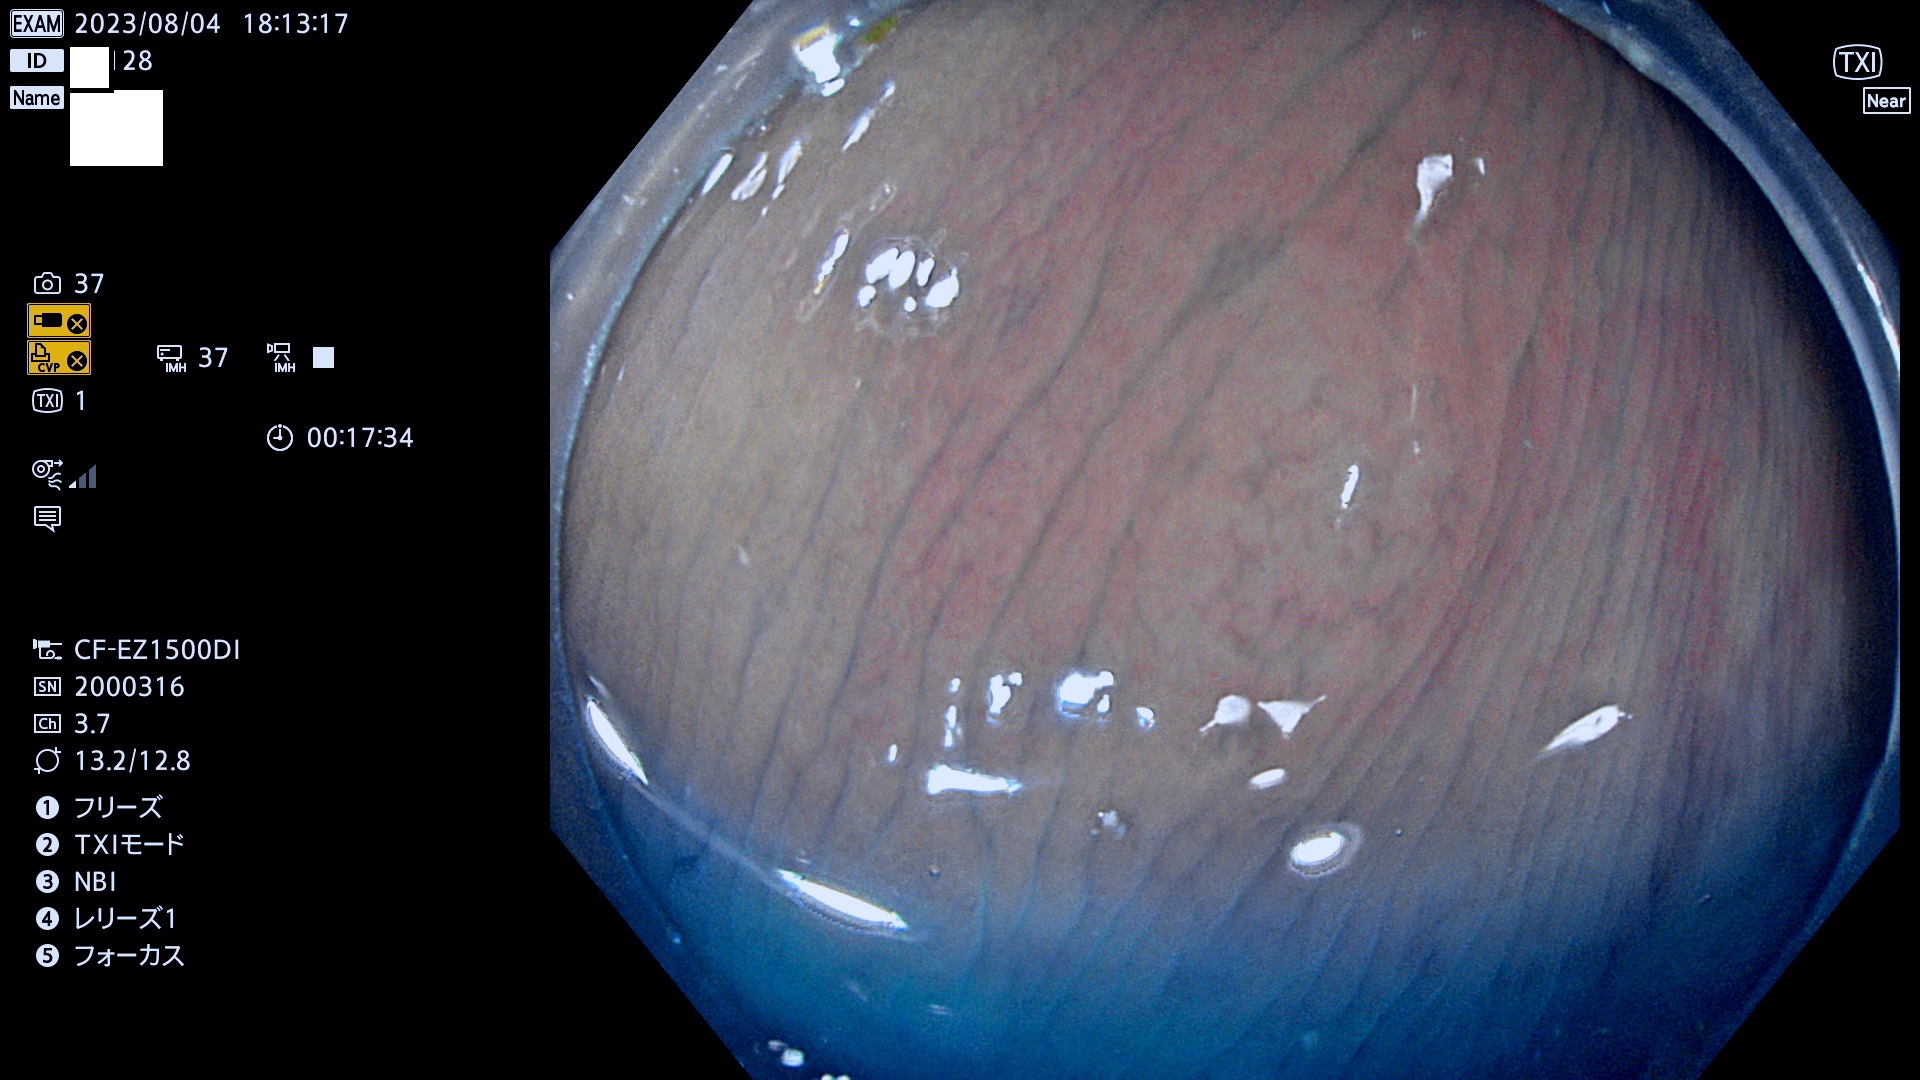

表面型腺腫(Flat Adenoma)の中で、完全に平坦な物をUb、陥凹している物をUcと呼びます。平坦隆起型(Ua)よりも、発見が難しく危険な病変です。このタイプは「内視鏡後・大腸癌の重要犯人」であり、この発見率は「腺腫発見率」よりも、重要な意味があります。

毎週の検査(木・金・土・日)に発見されたUb、Uc型・腺腫を、その週の日曜の夜にUPし1週間、提示します。

抽出の対象期間 2023年8月3日(木)〜8月6(日)の4日間(48件の検査)5件